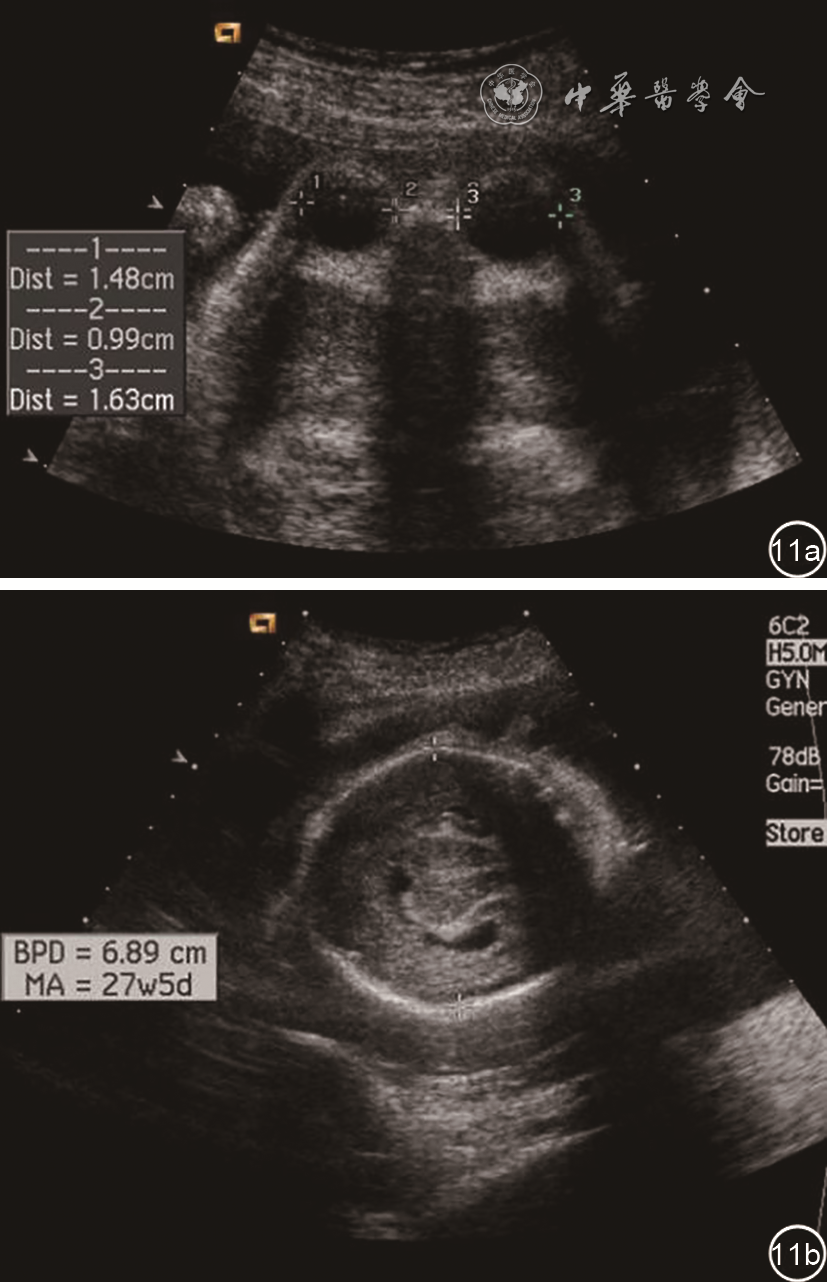

1. 眼距过近(Hypotelorism):眼距过近是两个眼眶相距很近。严重时两个眼球可以贴靠在一起,如贴靠在一起而仅有一眼眶时为独眼畸形。眼距过近的主要原因是前脑无裂畸形(图11),其他综合征很少有眼距过近表现。Mechel-Gruber综合征偶有此特征,某些染色体畸形、Williams综合征、小头等也可能有眼距过近表现。

图11 无叶全前脑胎儿超声声像图显示眼距过近。图a:双眼横切面示眼距过近,眼内距(0.99 cm)明显小于眼距;图b:丘脑水平横切面仅显示一个原始脑室,大脑镰及透明隔腔消失,丘脑不完全融合

影像学上眼距过近的诊断标准为眼内距小于正常孕周参考值的第5百分位。一般情况下,眼内径大约等于眼球直径,因此在双眼球水平横切面上,观察到眼内距小于眼球直径时,应怀疑眼距过近可能。发现眼距过近时,应仔细检查胎儿颜面部其他结构及颅内结构,如有无丘脑融合、单一原始脑室等,以排查前脑无裂畸形。胎儿颜面部三维超声检查在发现胎儿颜面部及眼畸形方面有一定价值,是二维超声的有益补充方法。

由于内分泌异常产前无法观察,产前超声在发现视觉通路异常,如眼球异常、脑中线缺陷、透明隔发育不良、胼胝体发育不良时,应注意排查本病的可能(图23)。其他与本病相关的异常包括脑裂畸形、脑室扩张、神经元迁移障碍、蛛网膜囊肿、脑干异常等。另外,可以观察视交叉结构判断视神经、视束的发育状况38,从而发现更多的诊断线索和依据。

图23 视隔发育不良胎儿产前超声声像图。27周胎儿,侧脑室水平横切面(图a)显示侧脑室增宽约1.16 cm;颅脑冠状切面(图b)显示透明隔腔缺失,侧脑室前角融合;侧脑室内壁(图c)不光滑,可见小点状突起(箭头),提示可能存在灰质异位;双眼球水平横切面(图d)显示右侧眼球较小;视交叉横切面(图e)测量显示视神经及视束直径小于正常。经全基因组

检查提示该胎儿存在SOX2基因缺失,该基因异常相关的综合征为视神经发育不全和中枢神经系统异常,或称为小眼综合征